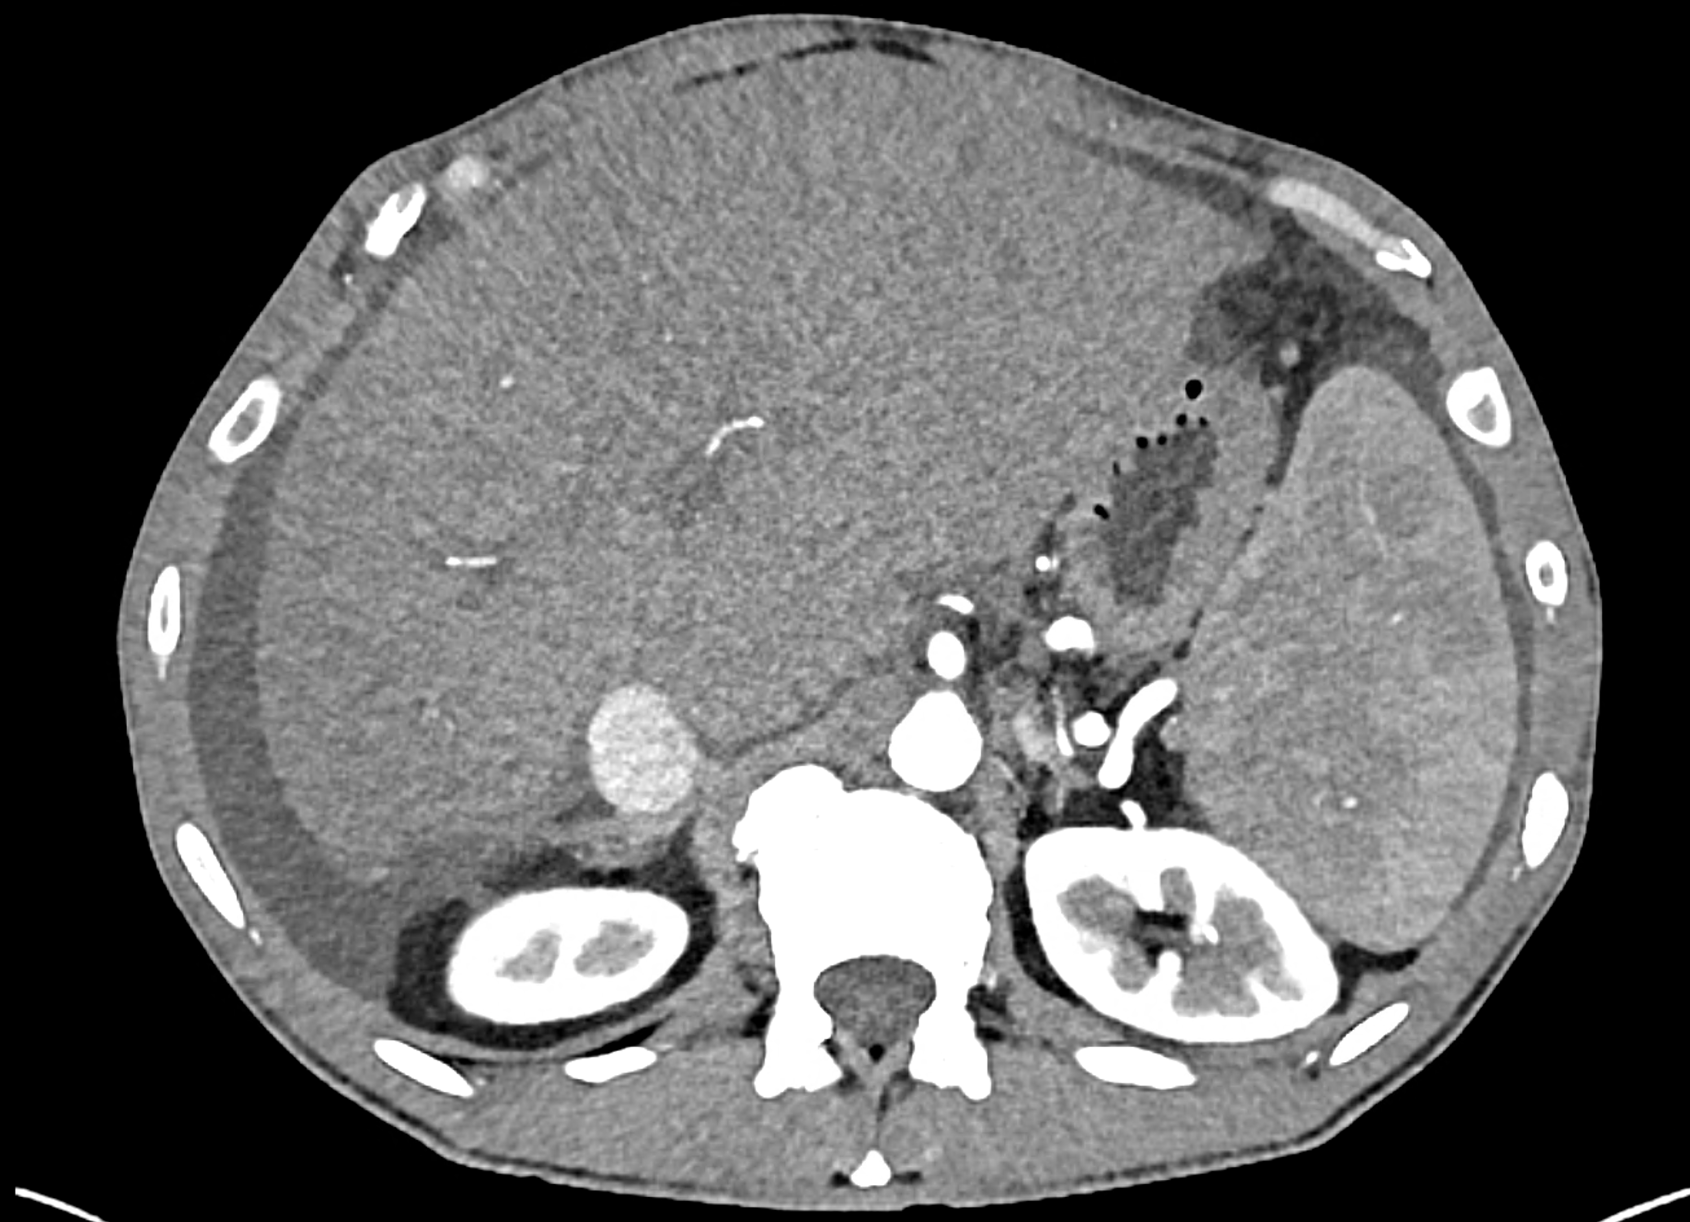

In CT images, BCS manifests as non-homogeneous enhancement of liver tissue in the arterial and especially in the portal phase, although in the portal phase may be increased, especially in the caudate lobe and left lobe, which are often hypertrophic (the hypertrophy and the enhancement is caused due to the possibility of the venous drainage directly into the inferior vena cava through the direct caudate veins), in contrast to the reduction in the right lobe. The portal vein is free, whereas even in the late phase, the hepatic veins and their contrast filling are not visible. Thrombotic occluded veins are hypodense.

A patient in his sixties with a Leiden mutation of factor V and a heterozygous prothrombin mutation presents with abdominal pain. Ultrasound examination reveals ascites and enlargement of the liver.There is enlargement of the liver, particularly the left lobe and caudate lobe. The hepatic veins are centrally filled with contrast medium due to reflux at the confluence with the inferior vena cava, and their radicular parts are thrombosed. There is typical chronic liver remodelling and the formation of centrifugal collateral circulation, including esophageal varices, and ascites is present in the abdominal cavity.

the axial images in the arterial, and the portal phases